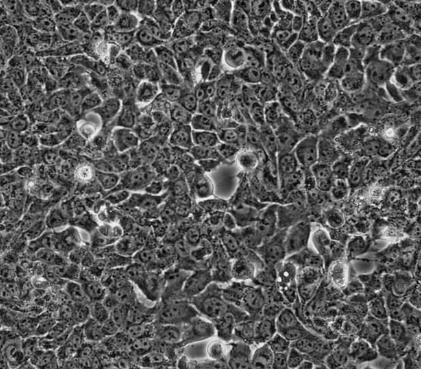

AML12,贴壁生长,上皮细胞样,呈多角形,直径约为20-30um,电镜下表现出典型的肝细胞特征,如过氧化物酶体和胆管状结构。AML12(小鼠肝12)细胞系是从携带人TGF-alpha基因的转基因小鼠(CD1株,MT42系)的肝细胞中构建的。AML12细胞保留了表达血清(白蛋白、α-1抗胰蛋白酶和转铁蛋白)和缝隙连接(连接蛋白26和32)的高水平mRNA的能力,并且只包含乳酸脱氢酶的同工酶5。

AML12